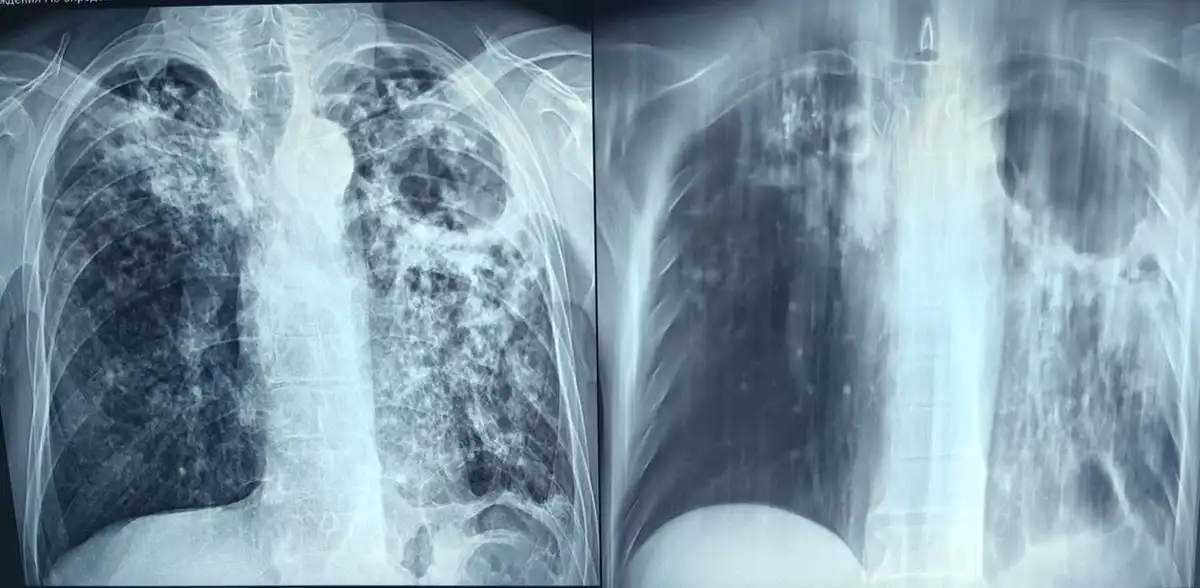

Флюорография не только выявляет туберкулёз, но и помогает заметить другие опасные заболевания на ранней стадии.

Ежегодно обследование проходят около 200 тысяч человек. Из выявленных заболеваний органов грудной клетки:

- 34 случая — туберкулёз (1,6%);

- 39 — онкология (1,9%);

- 1638 — сердечно-сосудистые патологии (78,7%);

- 355 — неспецифические болезни (17%).